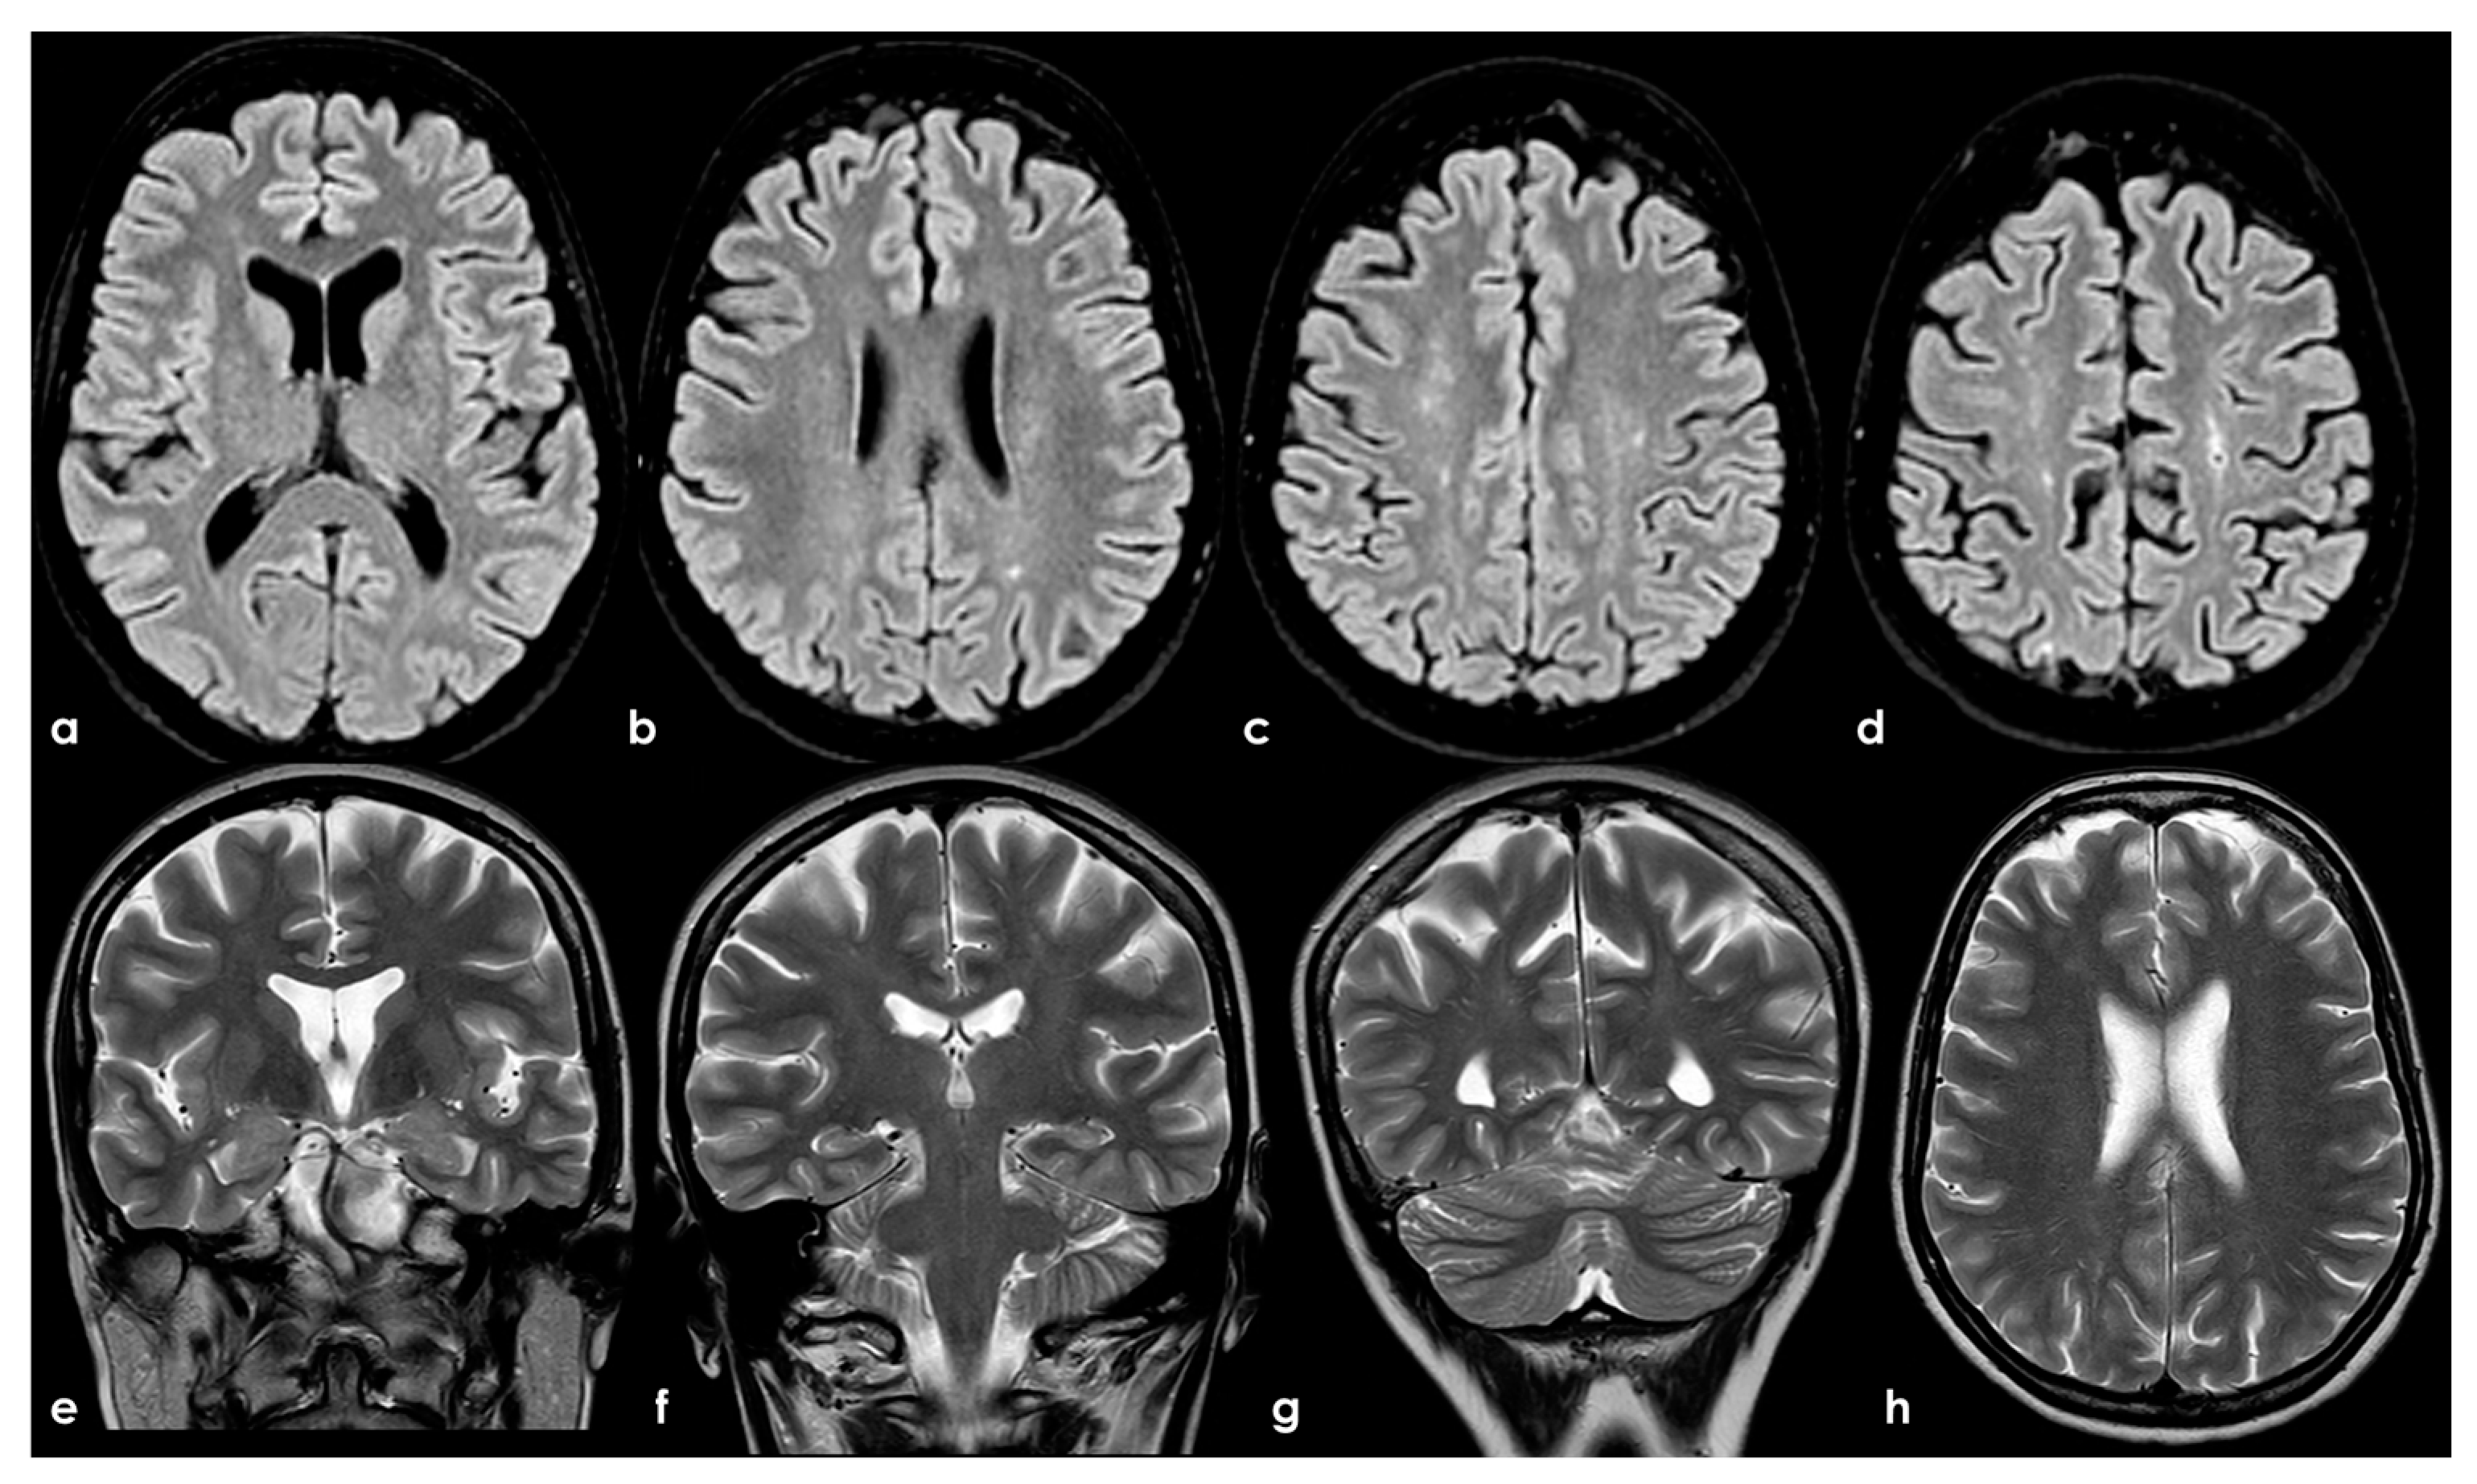

Figure 2.

Brain MRI (axial FLAIR in panels (a–d), coronal T2W in panels (a–g), and axial T2W in panel (h)) showing small punctate white-matter hyperintensities in the centrum semiovale, with a trend to watershed distribution (panel (d)), and a mild increase in enlarged perivascular spaces in the subcortical white matter (panels (e–h)).